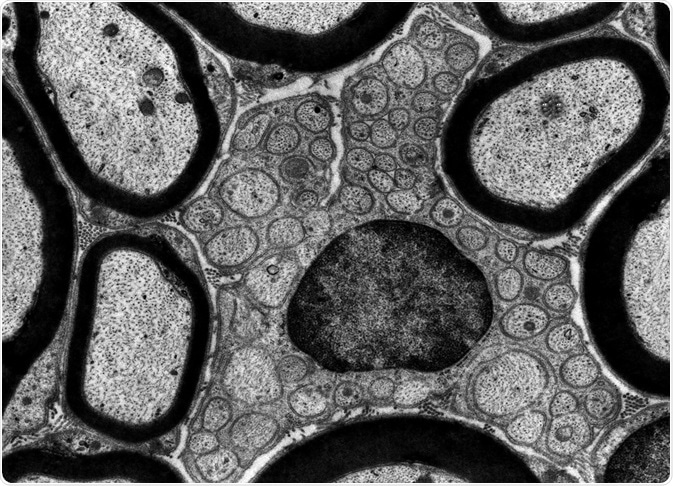

Credit: Jose Luis Calvo/ Shutterstock.com